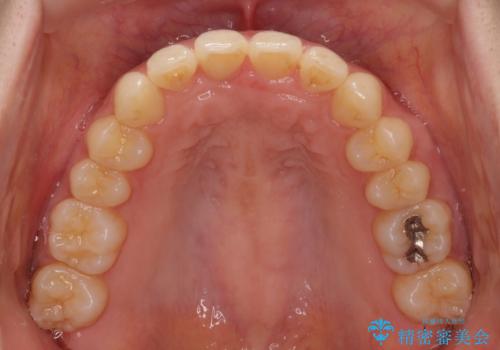

インビザラインによるディープバイトの改善

- 口元の前突感と深い咬み合わせ(ディープバイト)を気にして来院された患者様です。

インビザラインによる上下歯列の遠心移動(後方移動)と、それに伴う近心傾斜(前方傾斜)の改善により、口元の突出感とディープバイトを改善することとしました。

前歯のデコボコを最も気にしていましたが、咬み合わせが深く歯ぎしりが自由にできない点を指摘すると、常に食いしばってしまうことも悩みであることが分かりました。

咬合状態が大きく変化したため、治療後半では咬み合わせの位置が定まらなくなりました。上下の前歯に後戻り防止用のワイヤーを装着し、奥歯の咬合をフリーにしたことで1ヶ月ほどで咬み合わせが定まりました。